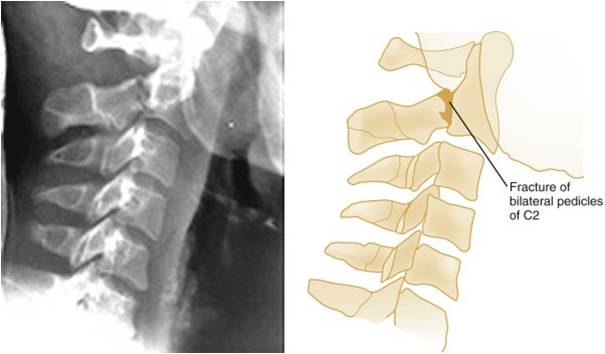

Hangman's Fracture

Mechanism: extension

Stability: unstable

Fracture lines extending through the pedicles of C2 are well visualized

Retropharyngeal soft tissue swelling is apparent